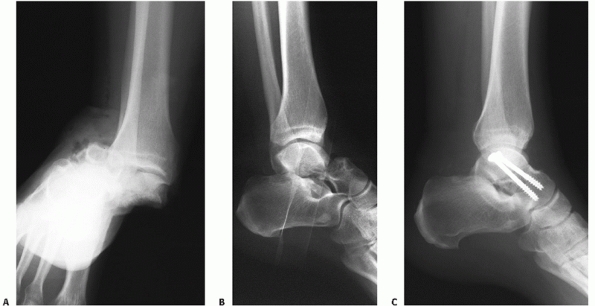

FIGURE 58-13

Closed reduction followed by posterior-to-anterior screw fixation of a noncomminuted type II fracture. The initial injury films are difficult to interpret but demonstrate a subtalar dislocation (A). An attempt at closed reduction partially reduced the subtalar joint but left residual subluxation (B). Formal closed reduction was accomplished in the operating room and stability was achieved with two posterior-to-anterior screws (C). |